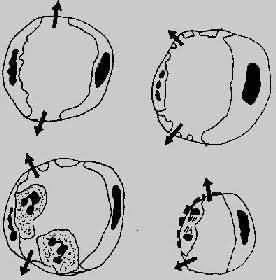

微循环血管通透性的维护,主要依赖于内皮细胞的完整性。在炎症过程中,下列机制可引起血管通透性的增加(图5-2)。

图5-2 血管通透性增加的四种机制模式图

左上图示内皮细胞收缩,累及细静脉;

右上图示直接损伤内皮细胞,累及全部微循环;

左下图示白细胞介导之内皮损伤,主要累及细静脉和毛细血管;

右下图示再生内皮细胞,主要累及毛细血管